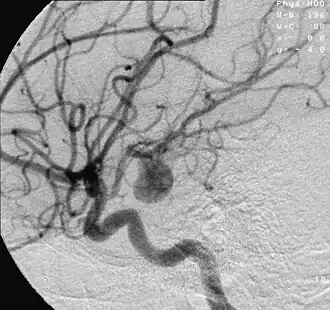

Аневри́зма (от др.-греч. ἀνεύρυσμα (aneúrusma) «расширение, растяжение») — выпячивание стенки кровеносного сосуда артерии (или, очень редко, вены), которое возникает в месте её перерастяжения, истончения и, как следствие, ослабления[1].

Аневризма может появиться и развиться в любой артерии. По форме аневризмы бывают мешковидными и веретенообразными[3].

- Ангиография («золотой стандарт» диагностики);